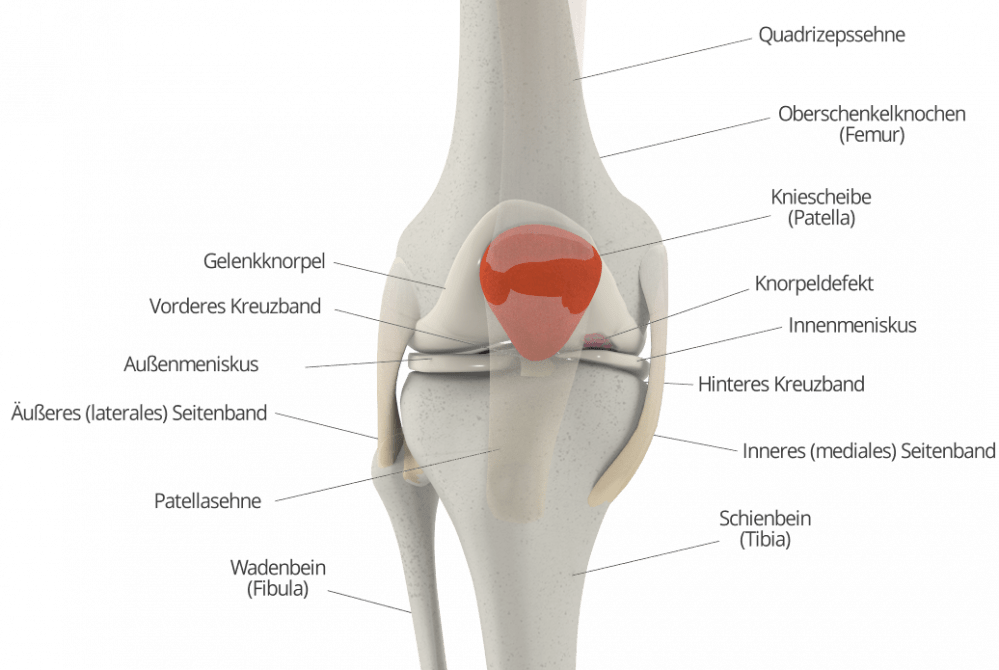

Der Begriff Chondromalazie leitet sich vom griechischen Wort „chondros“ für Knorpel ab und lässt sich frei mit „Knorpelerkrankung“ übersetzen. Definitionsgemäß handelt es sich um eine Knorpelerweichung. Das Kniegelenk ist besonders häufig von dieser Erkrankung betroffen. Sie kann aber prinzipiell in jedem Gelenk auftreten.

In den meisten Fällen ist eine Knorpelerkrankung die Folge einer Überlastung des Gelenkknorpels. Etwa durch exzessiven Sport oder anhaltende körperliche Belastung, zum Beispiel im Beruf. Auslöser kann aber auch ein Unfall und eine dabei entstehende Prellung oder Quetschung des Gelenkknorpels sein. In jedem Fall besteht ein Ungleichgewicht zwischen Belastung und Belastbarkeit des Gelenkknorpels im Knie oder in einem anderen Gelenk, was zu bleibenden Schäden führen kann.

Häufig kommt es bei Bewegung zu Knirsch- und Knackgeräuschen im Gelenk. Bei der klinischen Untersuchung lässt sich zudem häufig ein Druckschmerz im Bereich des Gelenkspaltes auslösen. Höhergradige Knorpelschäden schmerzen auch bei Belastung und Bewegung. In manchen Fällen bildet sich ein Erguss im Gelenk, der als Schwellung von außen sichtbar ist.

Mittels Röntgenaufnahmen lassen sich leichte Knorpelerkrankungen meist nicht erkennen. In einem MRT kann der Knorpel deutlich besser beurteilt werden. Eine Knorpelerweichung geht aber auch hier nicht zwingend mit sichtbaren Veränderungen einher. Erst wenn die Schäden schon fortgeschritten sind, verdichtet sich durch den erhöhten Druck der freiliegende Knochen, um der Belastung standzuhalten. Dies lässt sich sowohl im MRT als auch im Röntgenbild als sogenannte subchondrale Sklerose erkennen.

Tritt durch die konservative Therapie keine ausreichende Besserung ein, kann eine Operation erfolgen. Im Rahmen einer Gelenkspiegelung, der sogenannten Arthroskopie, kann die/der behandelnde Arzt/Ärztin das genaue Ausmaß des Knorpelschadens bestimmen. Mit Hilfe einer Knorpelzelltransplantation beispielsweise können Defekte im Gelenkknorpel geschlossen und damit ein Fortschreiten der Erkrankung verhindert werden. Langfristig lässt sich so der Ausweitung einer Chondromalazie zu einer Chondropathie und einer daraus entstehenden Arthrose vorbeugen.